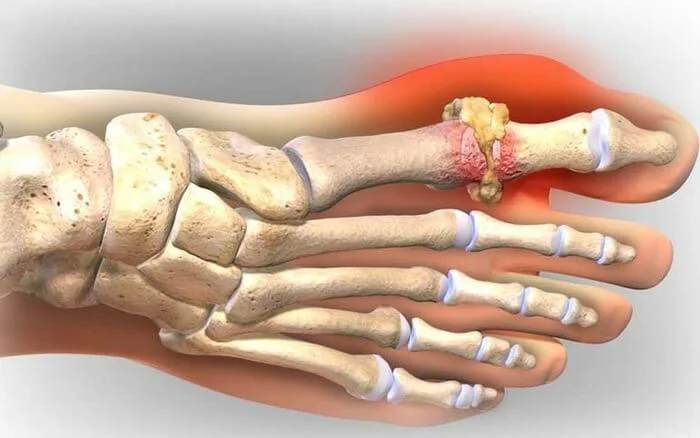

Нарост подагры

Нарост подНболь мазь, которую приготавливают следующим образом: залейте одно сырое яйцо (в скорлупе) уксусной эссенцией, плотно закройте и поставьте в темное место на 10-20 дней. Затем добавьте 150-200 грамм сливочного масла и перемешайте. Н

Также снимает боль мазь которую приготавливают следующим образом: залейте одно сырое яйцо (в скорлупе) уксусной эссенцией, плотно закройте и поставьте в темное место на 10-12 дней. Затем добавьте 150-200 грамм сливочного масла и перемешайте. Ногу парьте в течение 10 минут. Потом, держа ногу над паром, деревянной палочкой мажьте косточку, чтобы мазь при этом таяла. Из этой мази сделайте компресс на ночь. Процедуру повторяйте в течение двух недель. Сделайте перерыв на 2 недели и все повторите сначала.